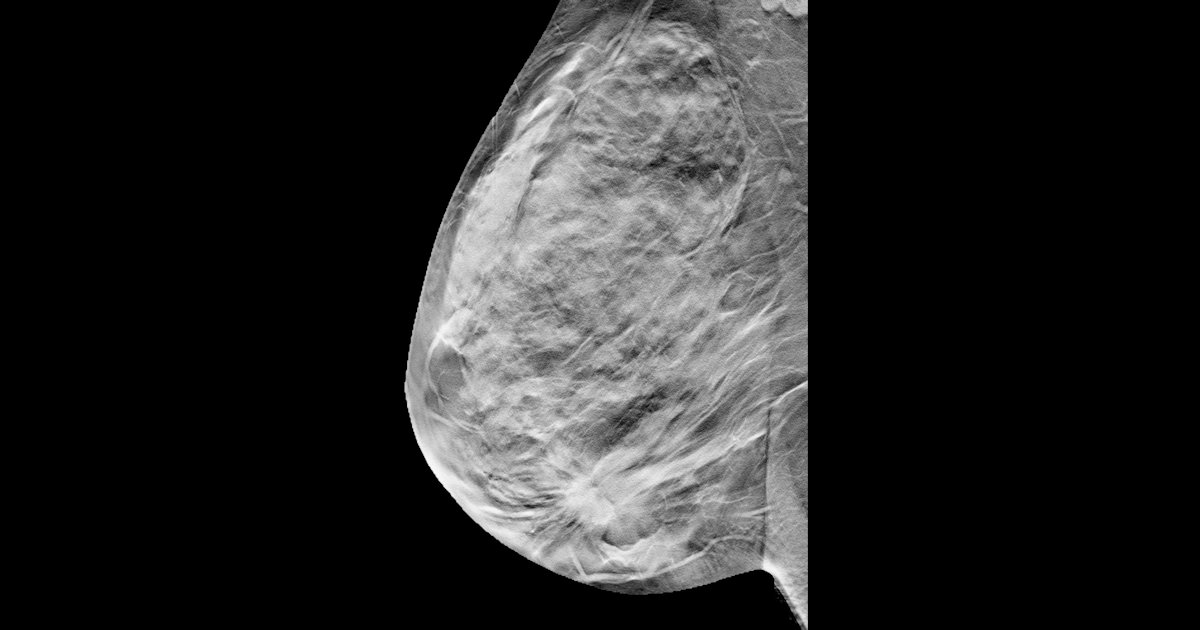

- Breast cancer screening's role is not clear in mortality trends. Countries with similar geographic locations and socioeconomic status experienced similar trends, no matter whether mammography screening had been in place since the 1980s or whether it was introduced in 2005 or later.